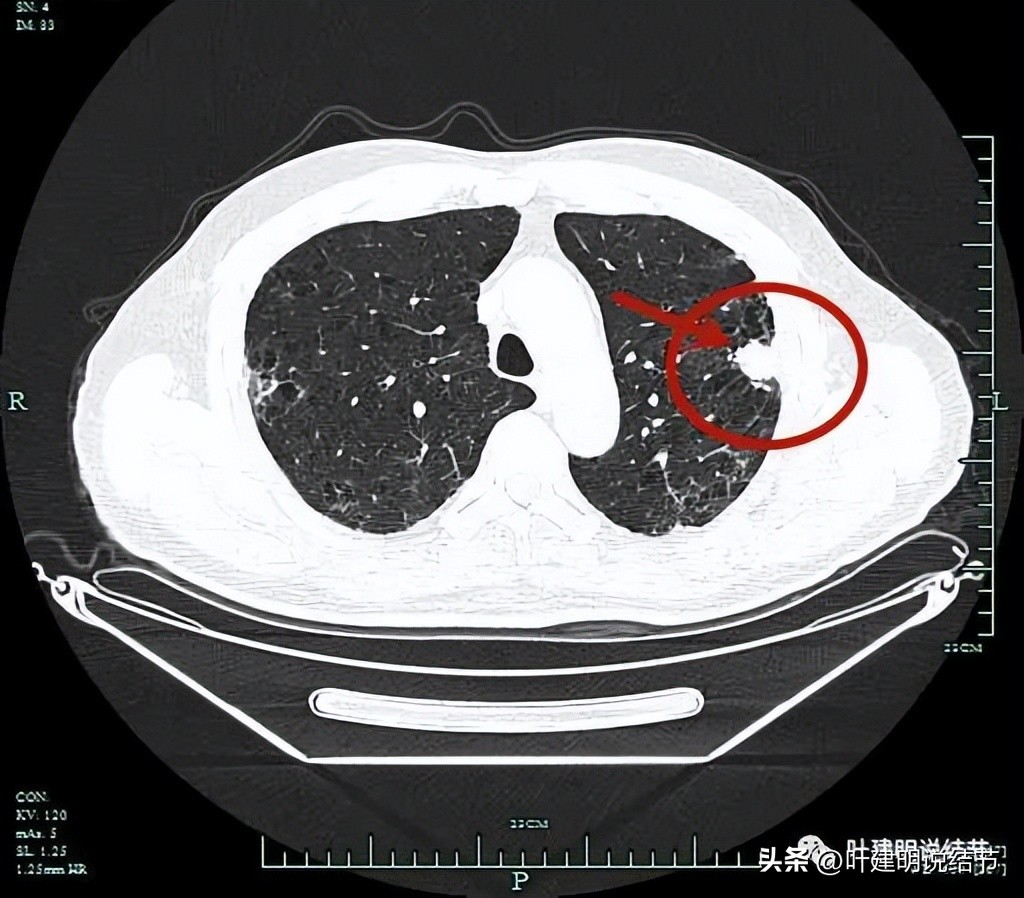

表面不平,分叶状。

分叶征(砖色箭头);毛刺征(紫色箭头);胸膜牵拉(蓝色箭头);病灶有膨胀感(红色箭头)。